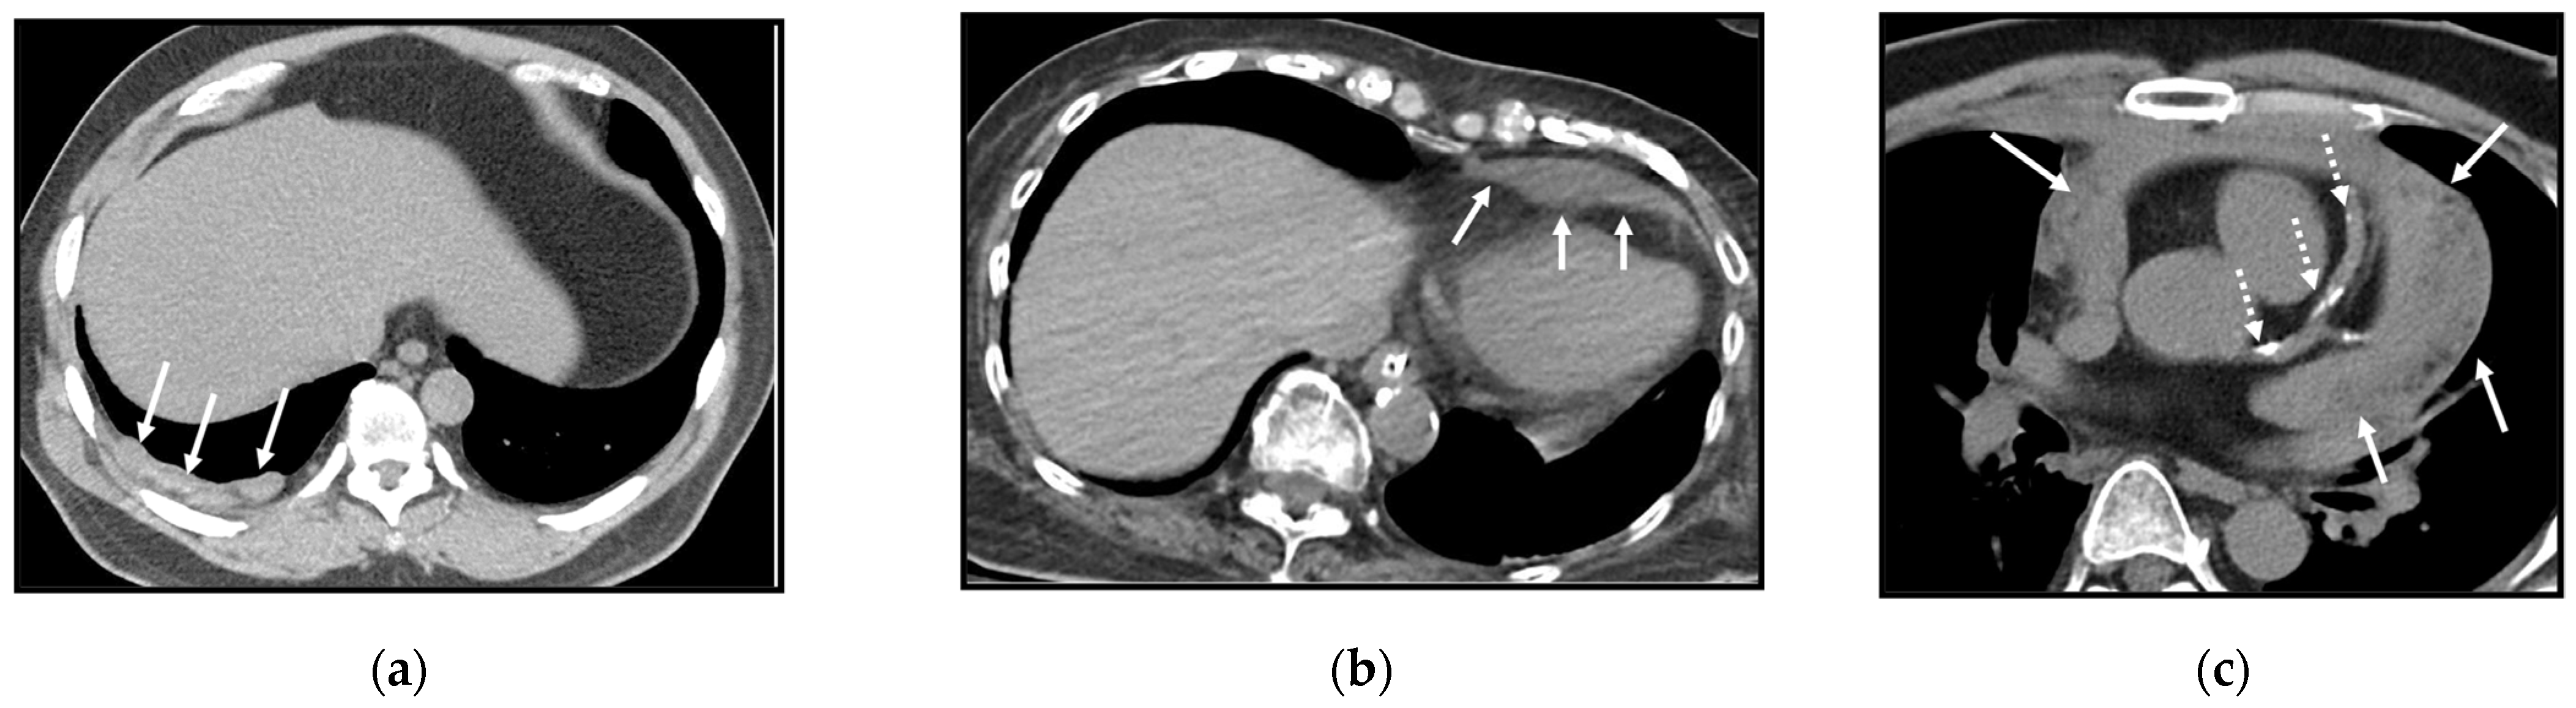

5.3.1. Liver

5.3.2. Adrenal Gland

5.3.3. Kidney